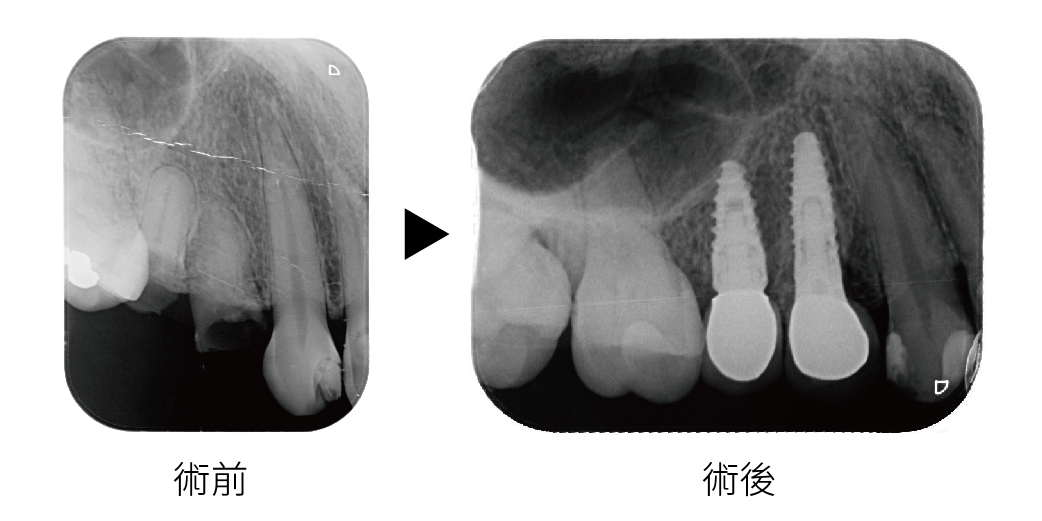

植牙後追蹤,從根尖片可以看出,骨頭與植體已完成骨癒合

確定治療計畫後,我們先進行了全口數位X光攝影與口腔3D掃描,評估骨質條件並規劃植體位置,由於患者缺牙區骨量略有不足,我建議同時進行微創補骨手術,以利後續植體穩固,術前我們詳細解釋每個步驟與可能的不適,讓患者充分了解流程並安心接受治療。

手術當天,採用局部麻醉,先將植體精準植入預定位置,再依據骨床狀態進行適量補骨,手術過程順利,術後僅有輕微腫脹與不適,經過幾天休息即恢復正常生活。